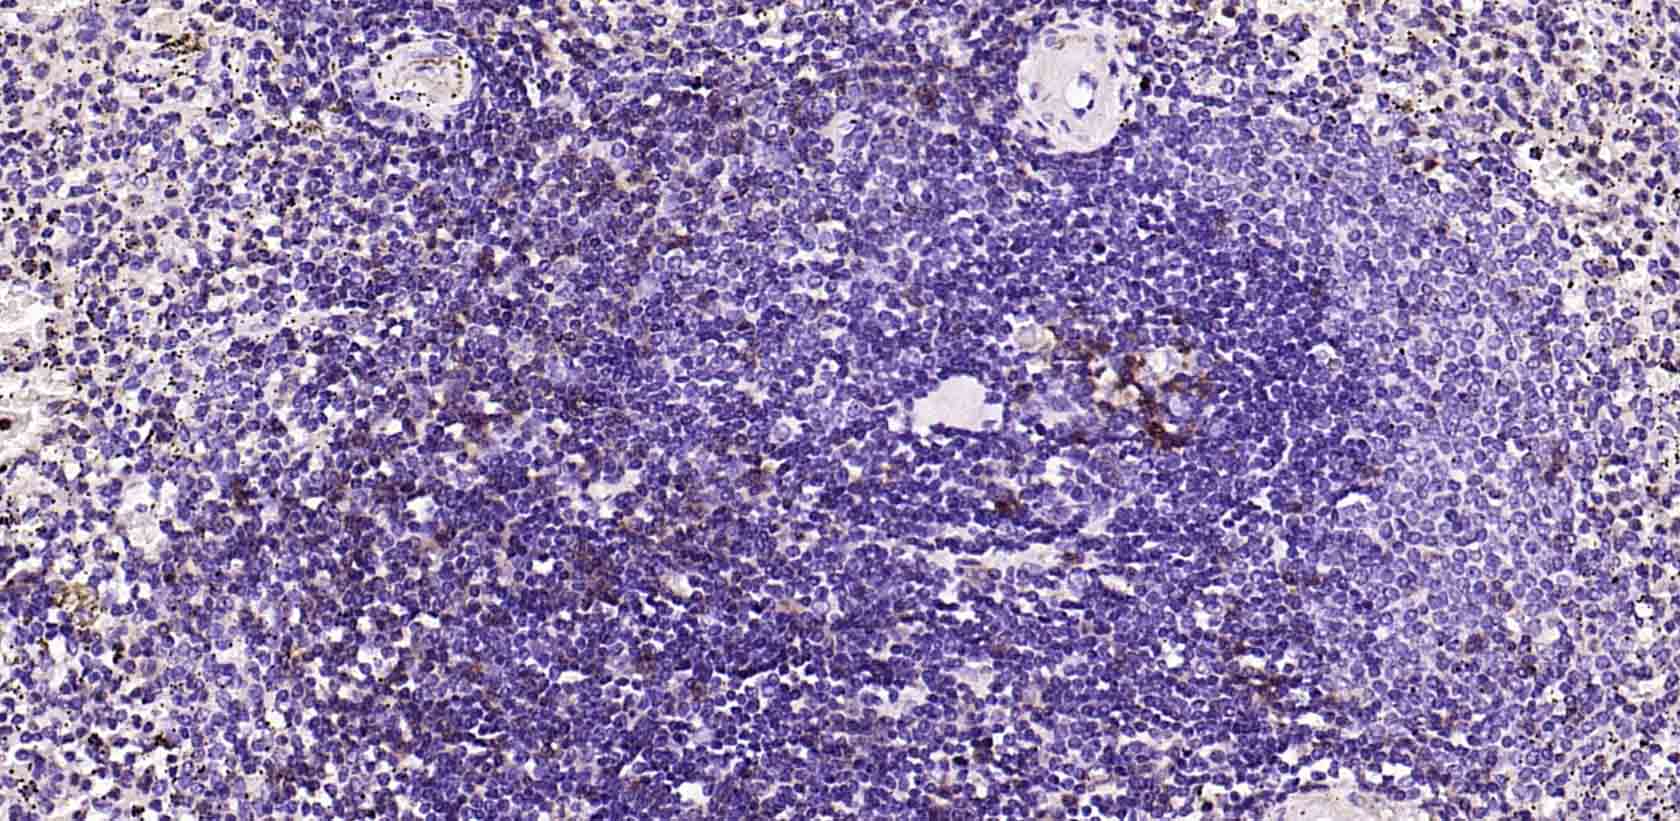

Paraformaldehyde-fixed, paraffin embedded Human Spleen; Antigen retrieval by boiling in sodium citrate buffer (pH6.0) for 15 min; Antibody incubation with PD-1 Monoclonal Antibody, Unconjugated(bsm-41117M) at 1:200 overnight at 4°C, followed by conjugation to the SP Kit (Mouse, sp-0024) and DAB (C-0010) staining.

Paraformaldehyde-fixed, paraffin embedded Human Tonsil; Antigen retrieval by boiling in sodium citrate buffer (pH6.0) for 15 min; Antibody incubation with PD-1 Monoclonal Antibody, Unconjugated(bsm-41117M) at 1:200 overnight at 4°C, followed by conjugation to the SP Kit (Mouse, sp-0024) and DAB (C-0010) staining.